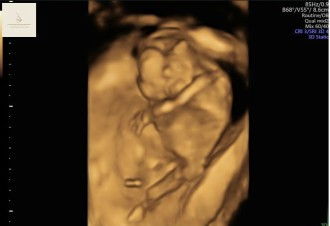

USG 15 minggu

Alhamdulillah Sehat Semua